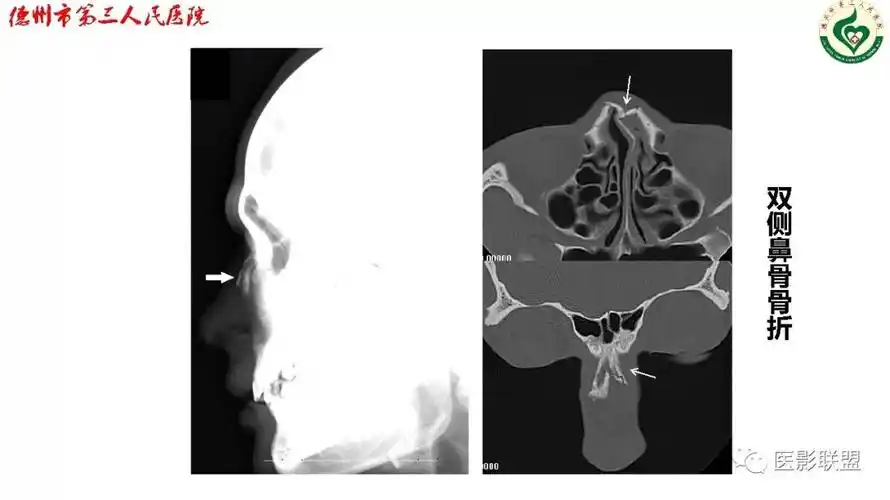

鼻骨解剖及骨折影像学诊断

鼻骨骨折影像学诊断

鼻梁上段塌陷或偏斜,皮下瘀血,x线鼻骨拍片或ct扫描可以显示骨折位置

鼻骨骨折影像学诊断与鉴别